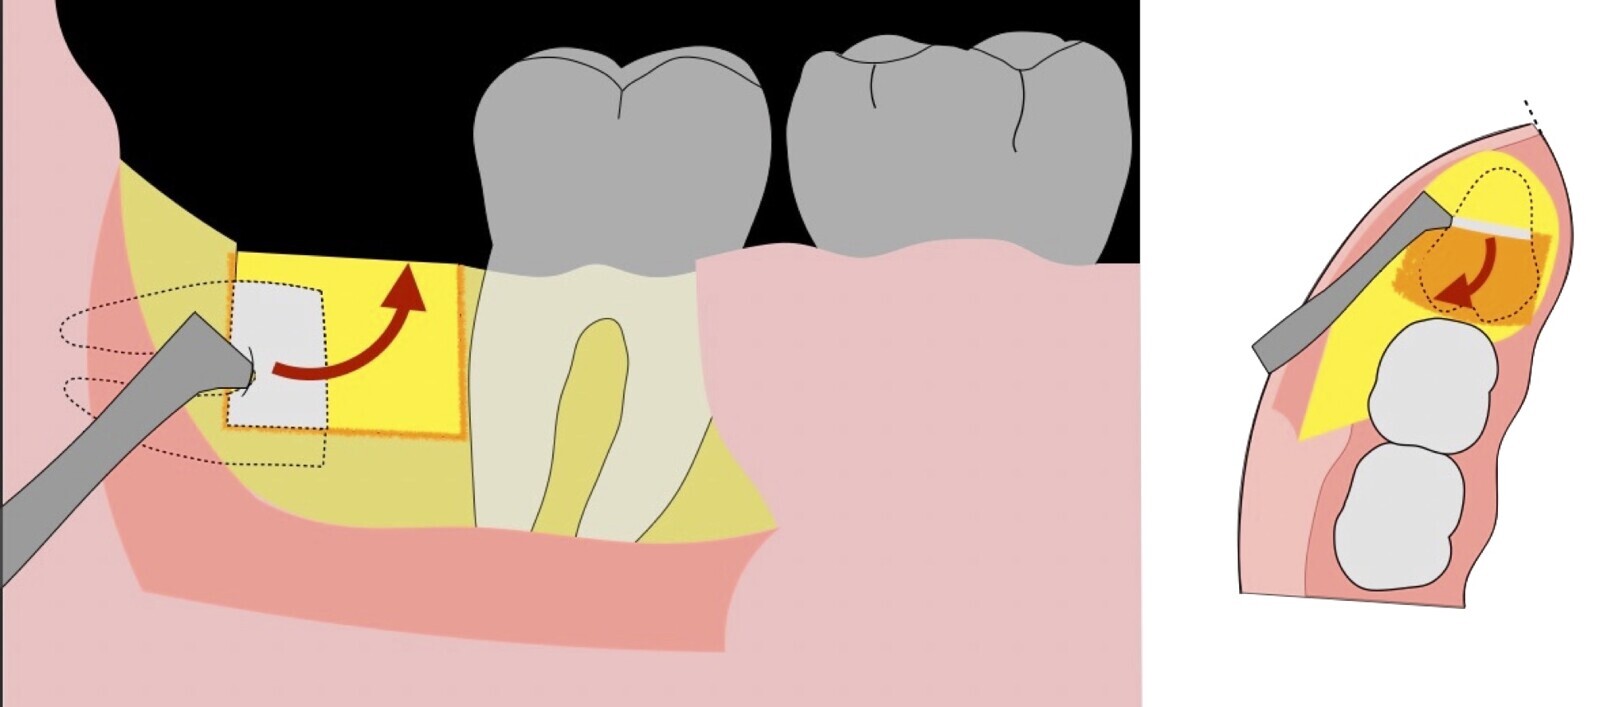

Figura 5. Fractura y eliminación oclusal del fragmento óseo de la porción coronal oclusal.

Figura 6. Demarcación y fractura de la zona de osteotomía a nivel vestibular con inserto aserrado recto y/o angulado.

Figura 7. Eliminación del fragmento vestibular.